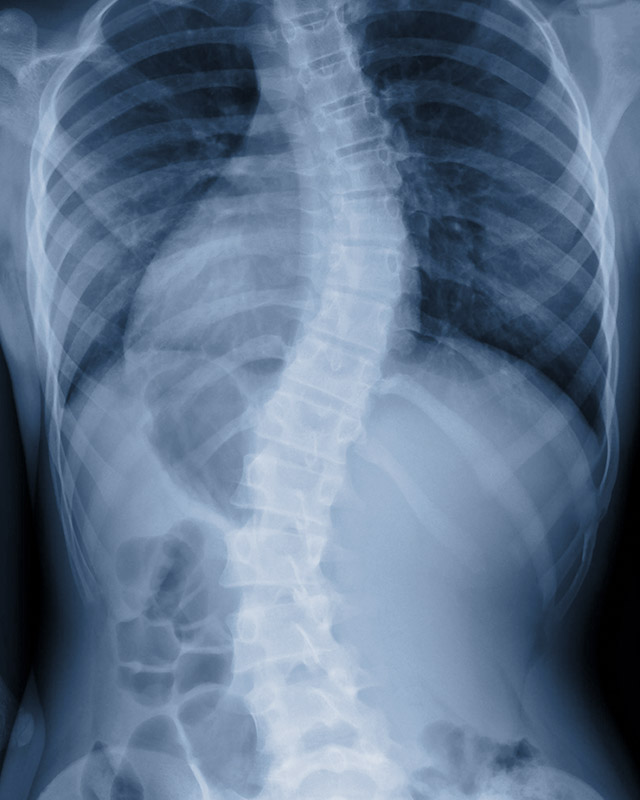

Scoliosis

Scoliosis is a very complex progressive spinal disorder. There are many causes of scoliosis and many approaches which may help reduce the symptoms, potential progression or improve scoliotic deformity. The effects of scoliosis include: poor posture, shoulder humping, muscle weakness, and pain. In rare cases scoliosis can lead to heart and lung problems.

If scoliosis is detected and treated early, patients can avoid these symptoms in many cases. If left untreated, scoliosis can sometimes require surgery. In surgical cases, the bones of the spine are sometimes fused together, and metal rods are inserted to try to straighten the spine. If the correct approach is used early enough, bracing is an effective treatment for halting the progression of scoliosis curves and reducing the need for surgery.

If you are concerned that your teenager has curvature of their spine I recommend you make an appointment to have their spine assessed, especially if there is a family history of scoliosis.

As a chiropractor I am skilled in the identification of scoliosis and I work closely with Scolicare Australia to provide the best way forward for each case.